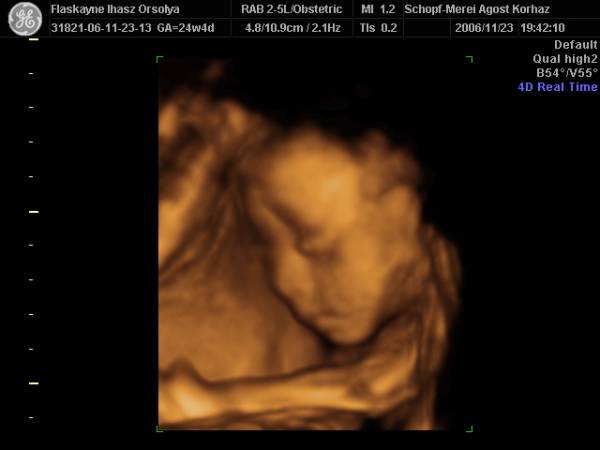

27.héten(Nagyon sokat változott,husis)